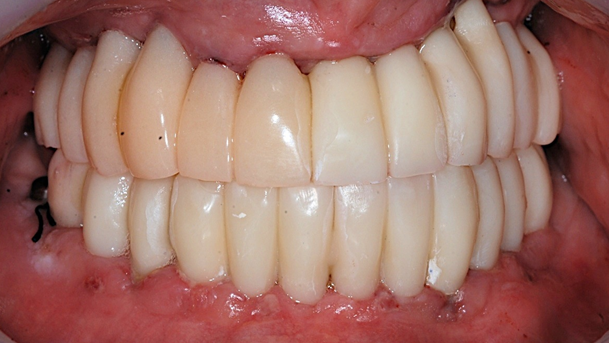

Dr. Sang Tack Lee, edentulous, digital full mouth prosthetics, digital guided surgery, #11, #13, #14, #16, #17, #21, #23, #24, #26, #27, #33, #34, #36, #37, #43, #44, #46, #47, guided surgery, flapless, AnyRidge, R2GATE, Mega ISQ, MEG Torq, MEG Engine, R2GATE Full surgical kit